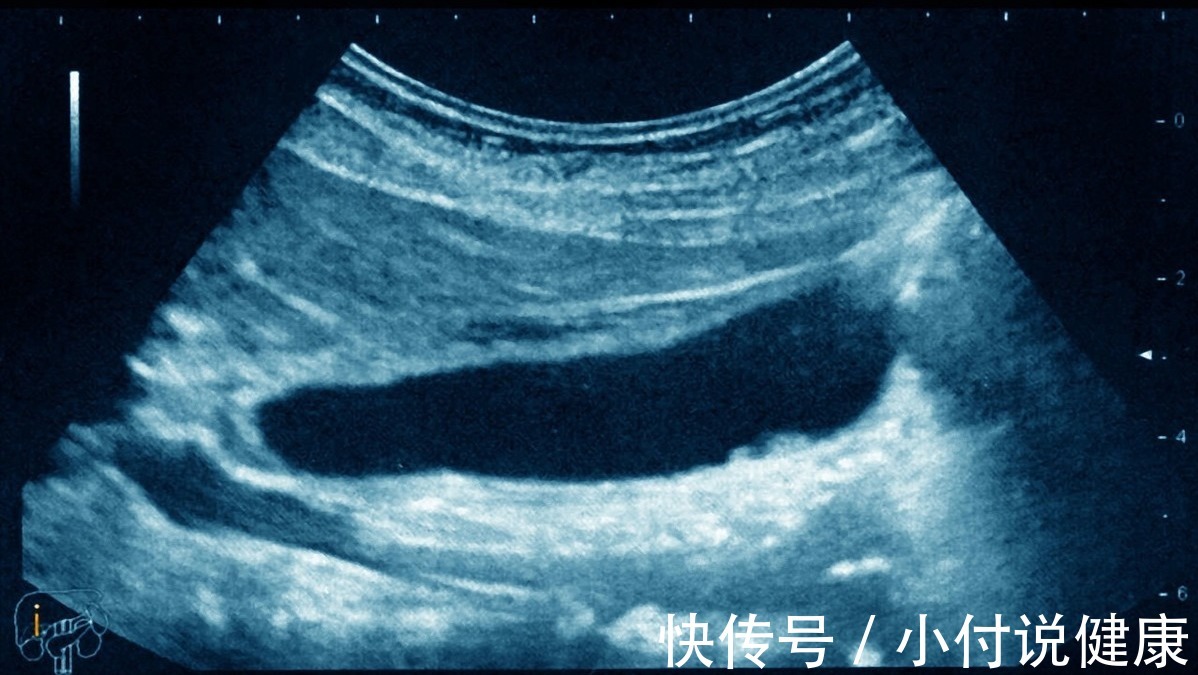

三、检查胆囊异常,选用B超即可B超是检查胆囊疾病的主要方式,可以比较准确的诊断出胆石症以及炎症的发生。因此来说,不管是急性还是慢性的胆囊炎,都可以采用B超的方式进行检查。若是怀疑有胆管结石的情况,也可以做MRCP 或者 ERCP 辅助检查。

对于慢性的胆囊炎患者而言,通过B超可以发现胆囊壁增厚、出现暗带、囊腔内出现回声、胆囊萎缩和结石等情况。而急性的胆囊炎患者做B超的话,可能会在影像中显示出肿大的胆囊、胆囊壁水肿增厚以及结石等现象。